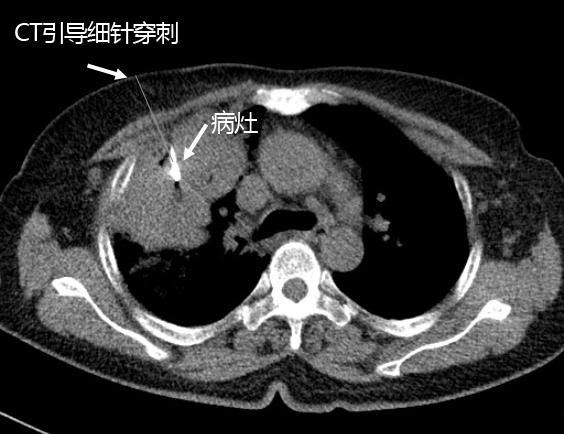

爲盡早确診肺癌的類型,制定科學的治療方案,内三科李旭丹主任爲患者施行經皮肺細針穿刺活檢術。通過西門子128層CT對腫塊精準定位,李主任娴熟操作穿刺針在最佳穿刺點進針,在CT持續引導下按預定的進針角度和深度,精準到達病竈部位,提取病竈内的細胞做病理學檢查。

通過病理檢查結果确診爲右肺腺癌,李主任随即根據該型肺癌特點結合患者身體情況,爲其制定個性化治療方案,爲患者争取到了寶貴的治療時機,取得良好治療效果。

據李主任介紹,如何鑒别肺結節良、惡性,以及如何對肺腫瘤進行病理分型、臨床分期,最終确定采取何種治療方法是肺部腫瘤精準治療的難點,而經皮肺細針穿刺活檢術爲上述難點找到了解決方法。通過CT引導下,行細針穿刺活檢術精準提取病竈内細胞進行病理檢查,被譽爲确診肺腫瘤的金标準。1月份以來我院已經通過此技術确診出2例周圍型肺腺癌、1例周圍型肺鱗癌,爲制定個性化科學治療方案提供依據。同時采用上面方法還确診1例慢性肺膿腫患者,通過抗感染治療後,病竈消失患者康複出院。

目前省城三甲醫院對符合該術适應症的患者,已經常規開展經皮肺穿刺活檢術,該術不會傷到周圍組織,由CT引導準确提取病竈細胞,整個過程隻需10-20分鍾即可完成,傷口僅針孔大小,術後貼下創可貼并稍作休息即可。微創、快速、準确是細針穿刺活檢術的主要特點。